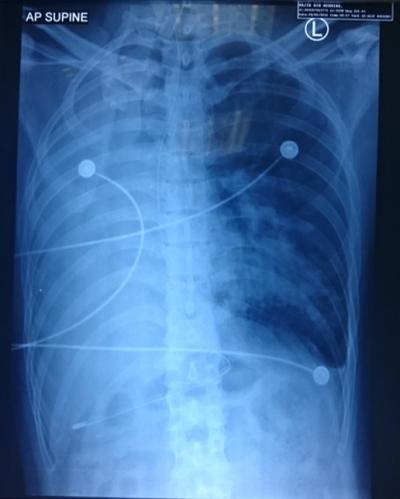

Figure 1: CXR post-intubation before any bronchoscopy and suctioning intervention. Right lung atelectasis and shifting of trachea towards right lung noted.